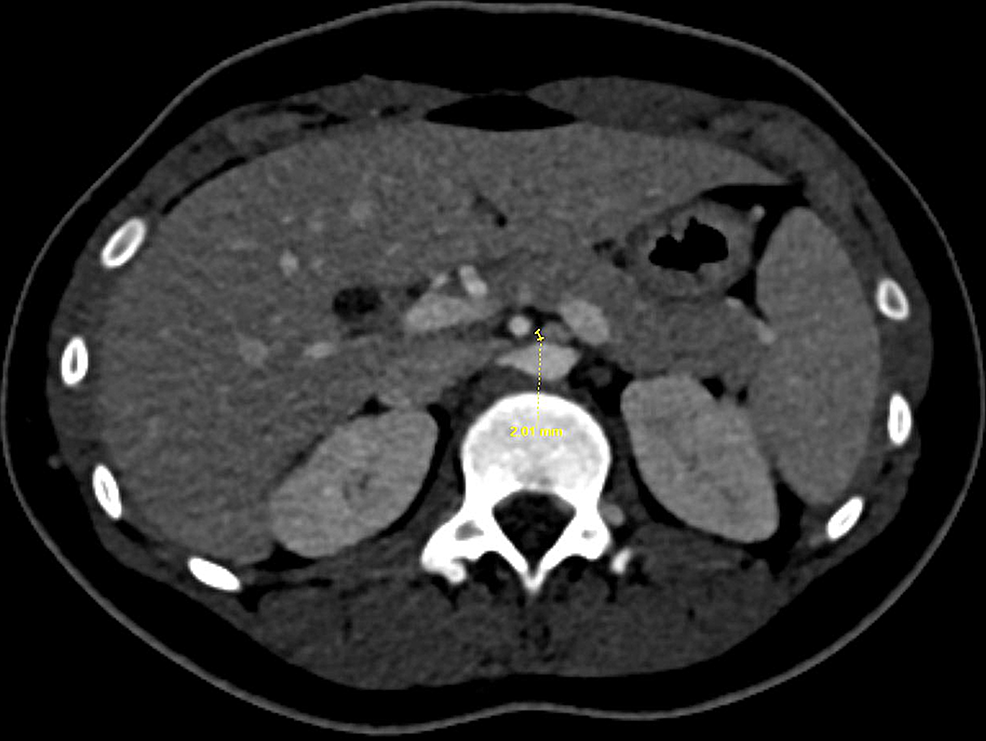

Nutcracker syndrome (annotated CT) Image Nutcracker Syndrome Abdominal Pain Other indications include failed conservative measures after 2. Nutcracker syndrome (ncs) is an extrinsic compression of the left renal vein (lrv) by the superior mesenteric artery (sma). Operative intervention should be considered for adults with gross hematuria, especially for patients requiring transfusion or with recurrent episodes, and for patients with such severe flank or abdominal pain that narcotic pain medication. Nutcracker Syndrome Abdominal Pain.